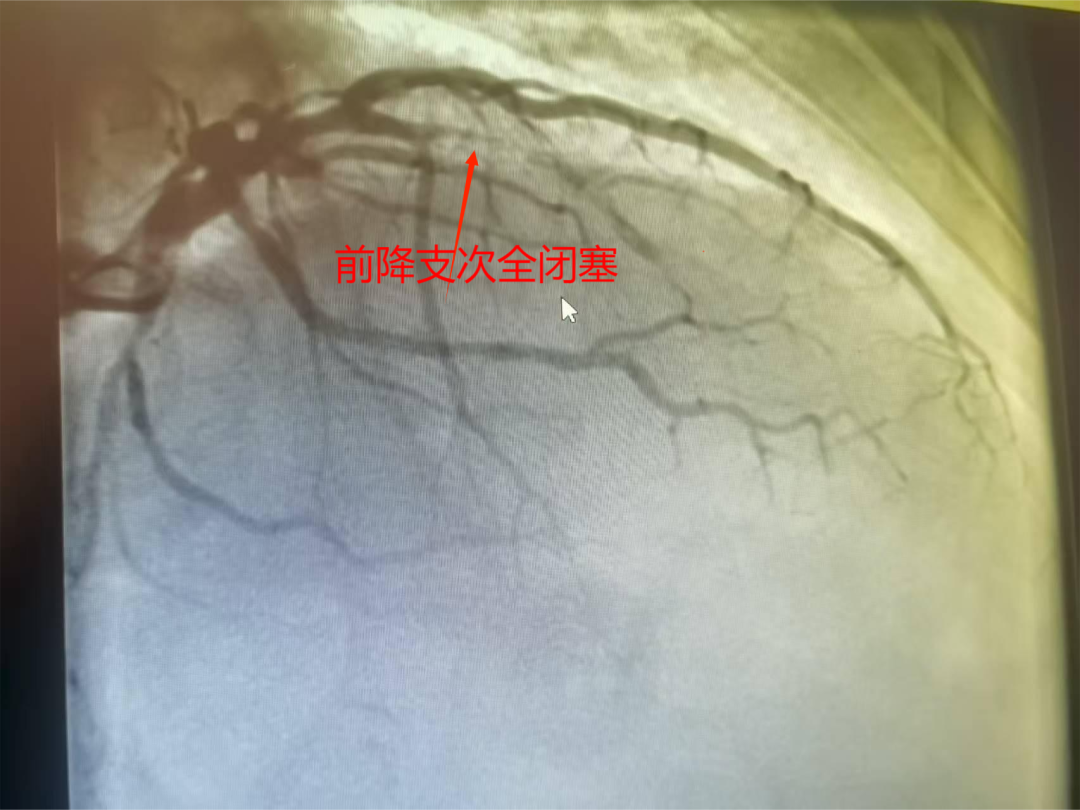

一位60多岁的男性患者,因反复胸痛长达一月,前来我院入院治疗。经冠状动脉造影检查,结果显示其前降支近中段呈现次全闭塞状态,且伴有明显钙化。

术前造影前降支血管次全闭塞